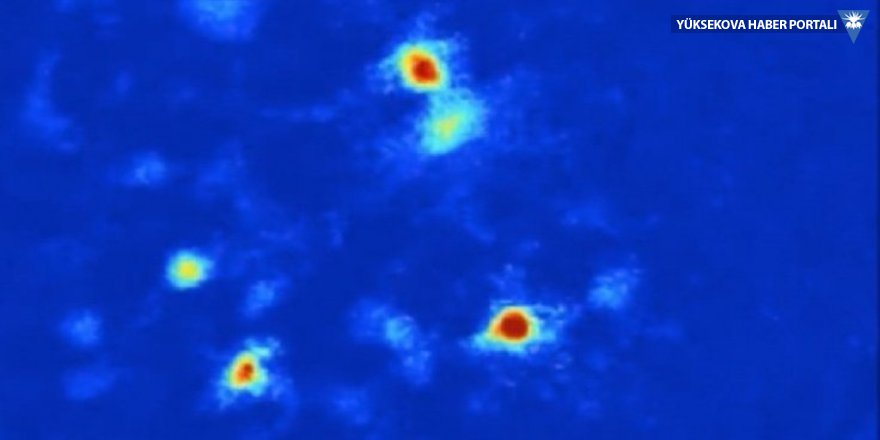

Ekip bunu anlamak için, “kalsiyum görüntüleme” adı verilen bir teknik kullandı ve laboratuvar farelerinin beyinlerine minyatür mikroskoplar yerleştirerek, hayvanlar bulundukları kafes içerisinde hareket ettikleri sırada hipokampus bölgesindeki hücrelerin oluşumunu kaydetmeyi başardılar.

Yanına sığındıkları duvarların sağladığı güvenlik hissinden uzakta olan farelerin beyinlerinde bazı değişimler fark edildi; araştırmacılar, hipokampus bölgesinde bulunan ve “ventral CA1″ (vCA1) adı verilen bir bölümde oluşan hücreleri izlemeye aldı ve farelerin hareketleri arttıkça, nöron (beyin hücresi) faaliyetlerinin de aynı oranda yükseldiğini keşfetti.